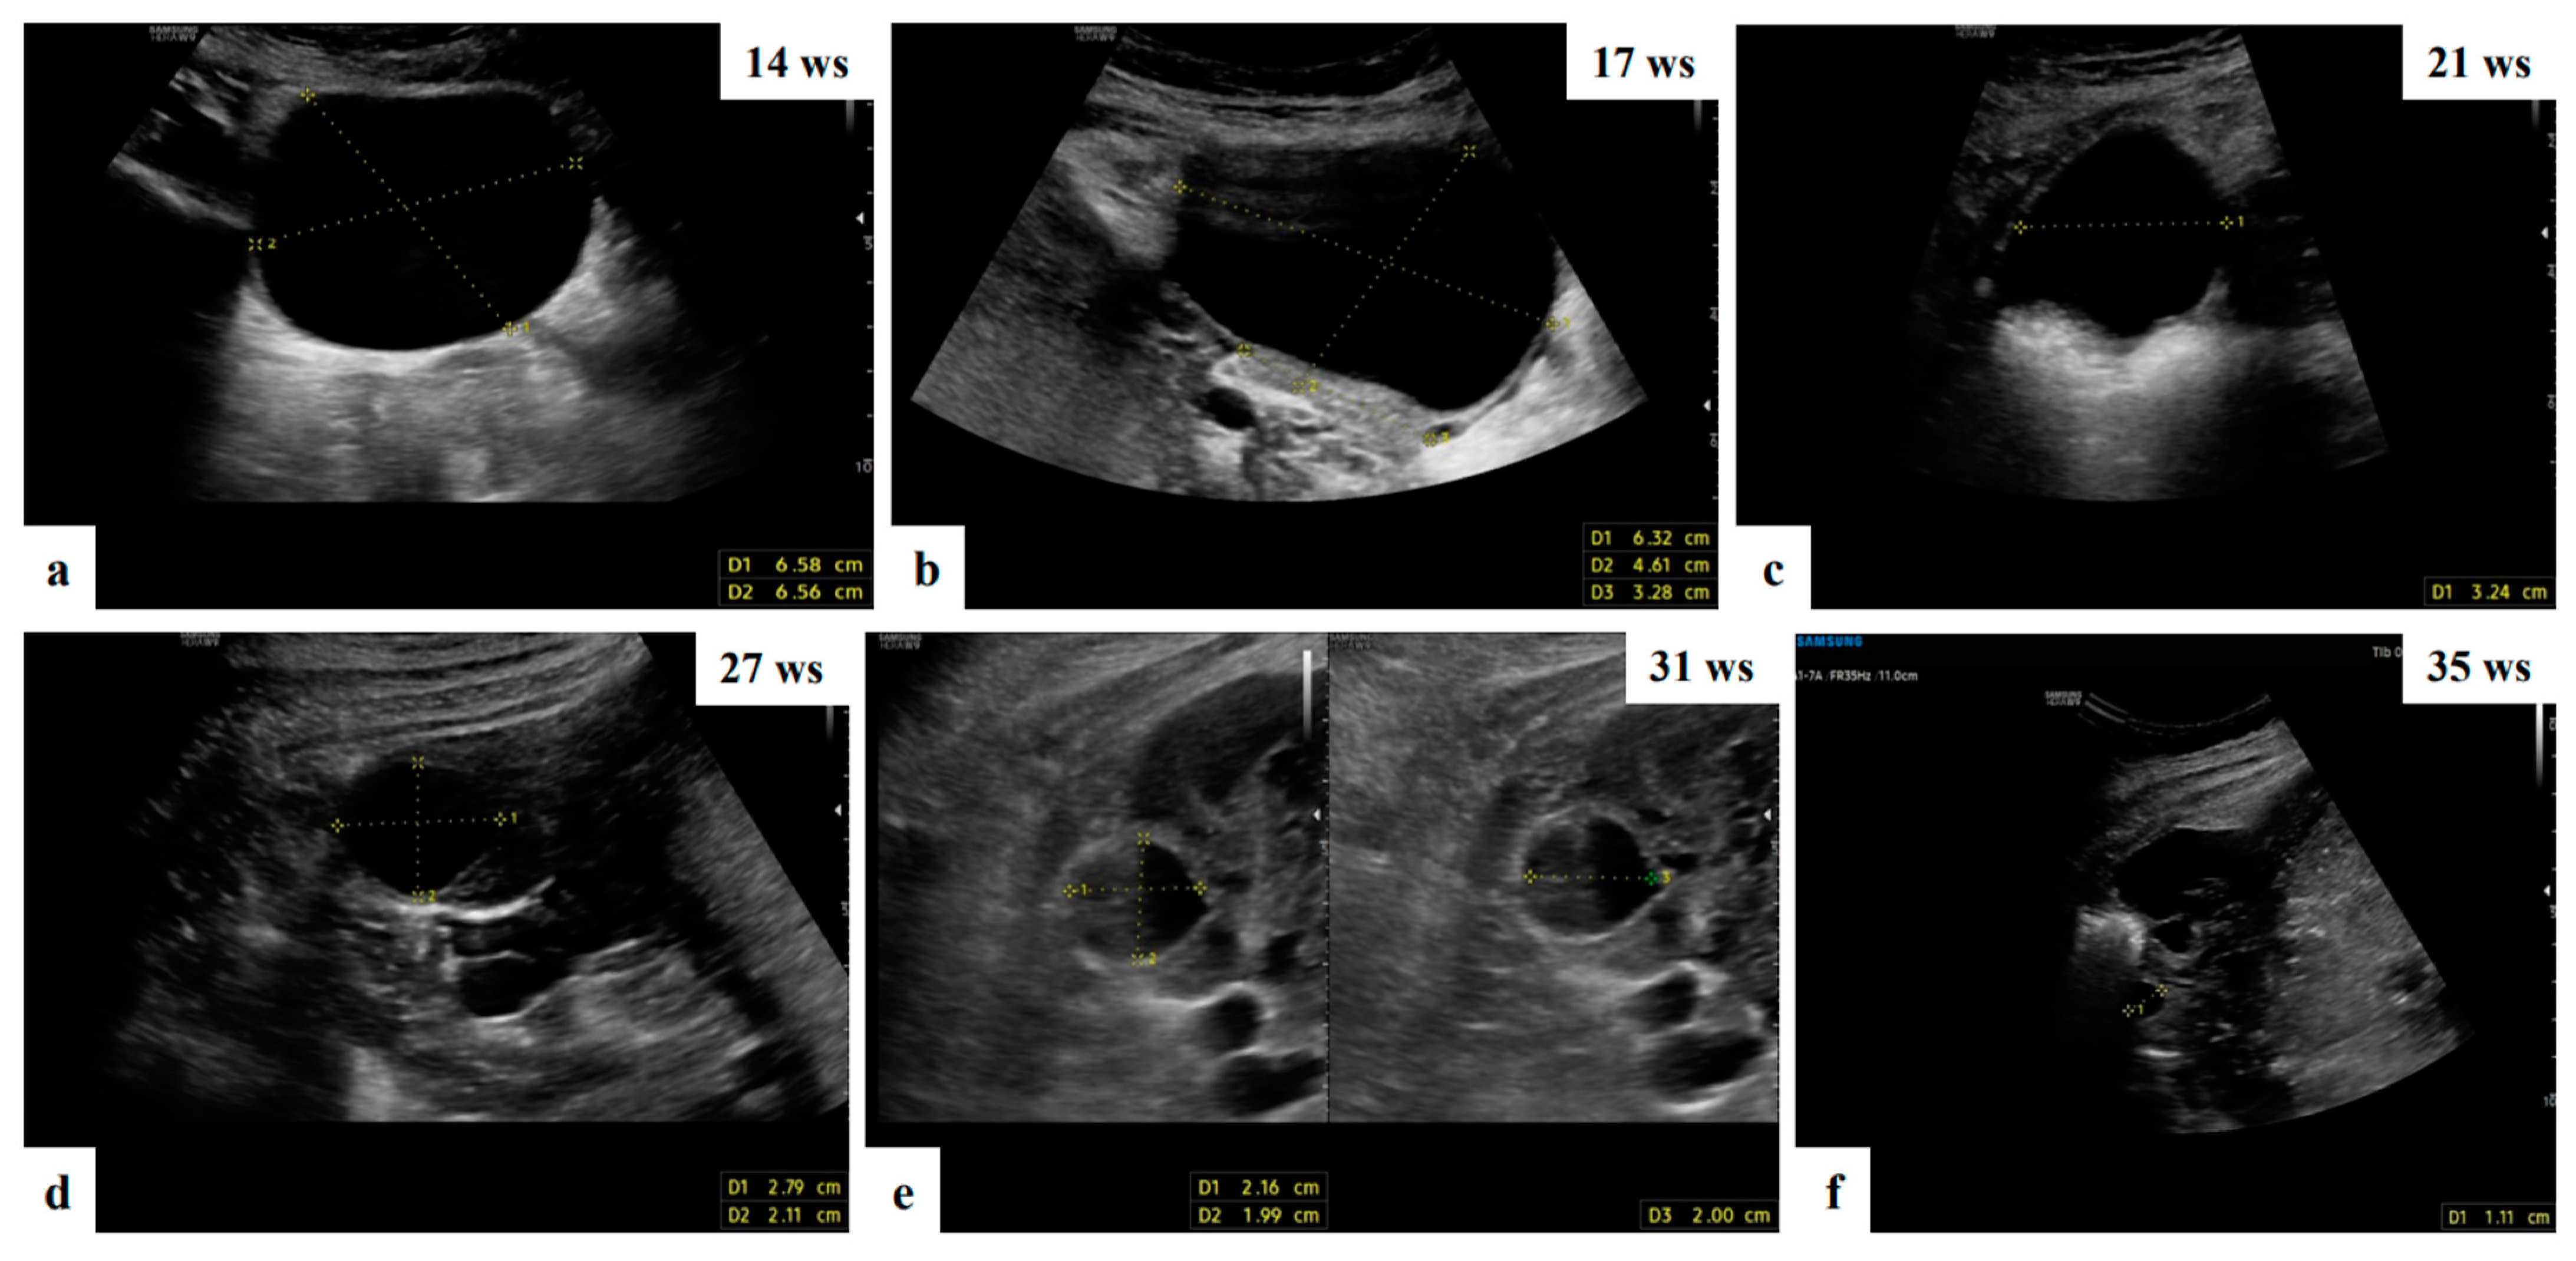

- Mascilini, F.; Moruzzi, C.; Giansiracusa, C.; Guastafierro, F.; Savelli, L.; De Meis, L.; Epstein, E.; Timor-Tritsch, I.E.; Mailath-Pokorny, M.; Ercoli, A.; et al. Imaging in gynecological disease. 10: Clinical and ultrasound characteristics of decidualized endometriomas surgically removed during pregnancy. Ultrasound Obstet. Gynecol. 2014, 44, 354–360. [Google Scholar] [CrossRef]

- Pateman, K.; Moro, F.; Mavrelos, D.; Foo, X.; Hoo, W.L.; Jurkovic, D. Natural history of ovarian endometrioma in pregnancy. BMC Women’s Health 2014, 14, 128. [Google Scholar] [CrossRef]